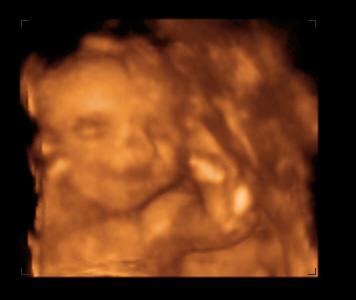

Egyúttal bemutatnám Emma babámat! Ma voltunk 4D-n nagy élmény volt. Hát íme a kis mosolygós:

Kép